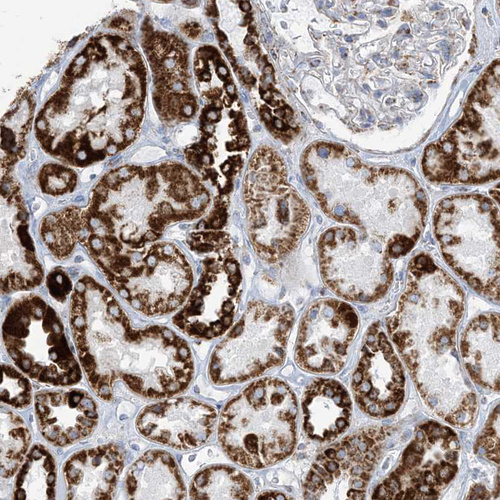

Immunohistochemistry analysis in human kidney and pancreas tissues using HPA034537 antibody. Corresponding SAMM50 RNA-seq data are presented for the same tissues.